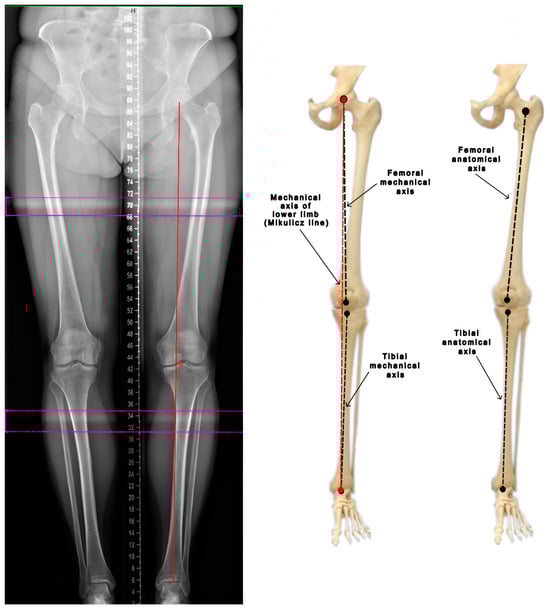

The anatomical axes of the femur and tibia align with the mid-diaphyseal line of each respective bone. The mechanical axis of the femur is defined by a line extending from the center of the femoral head to the center of the femoral intercondylar notch. Similarly, the mechanical axis of the tibia is delineated from the interspinous groove to the center of the talus or tibial plafond. Consequently, in the tibia, both axes are physiologically similar to each other. An additional mechanical axis of the lower limb, known as the Mikulicz line, is defined by a line that extends from the center of the femoral head to the midpoint of the tibial plafond (the center point of the ankle joint) (Figure 1). The lateral or medial deviation of this axis from the center of the knee joint is measured in millimeters, and this range is referred to as the mechanical axis deviation (MAD). In the correct physiological position, the Mikulicz line should run approximately 4 ± 2 mm medial to the center of the knee. The line’s course is indicative of specific alignment issues: a lateral deviation suggests valgus alignment, while a more medial deviation indicates varus alignment. The joint line convergence angle (JLCA) is formed by a line that touches the femoral condyles and a line that touches the tibial plateau. Under normal conditions, these lines are nearly parallel, showing a slight medial convergence of 0–1 degrees. In valgus knees, the JLCA opens medially, while in varus knees, it opens laterally [8,9,10].

Figure 1. Evaluation of the mechanical and anatomical axes of the lower limb (based on Luís et al. [8]).